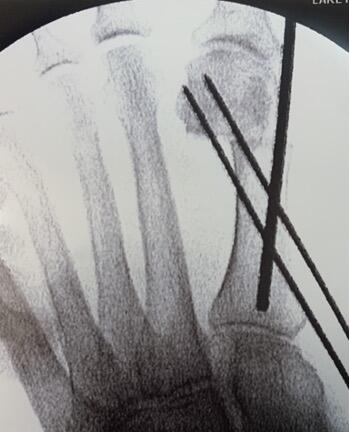

The surgeon can then confirm the trajectory and depth of the burr with fluoroscopy. In our experience and from what we have learned, the initial pass of the burr should be a direct drill hole, straight through the medial and lateral cortex of the first metatarsal neck (see second photo above). The entry point of the burr within the medial cortex should remain static for the entirety of the osteotomy. The remainder of the osteotomy then takes place around this pivot point. The hand should rotate plantarly for the dorsal portion of the osteotomy, perpendicular to the long axis of the metatarsal. Conversely, the hand will rotate dorsally to complete the osteotomy through the plantar cortex. Methods may vary, such as a “poke and drag” technique or working in quadrants.